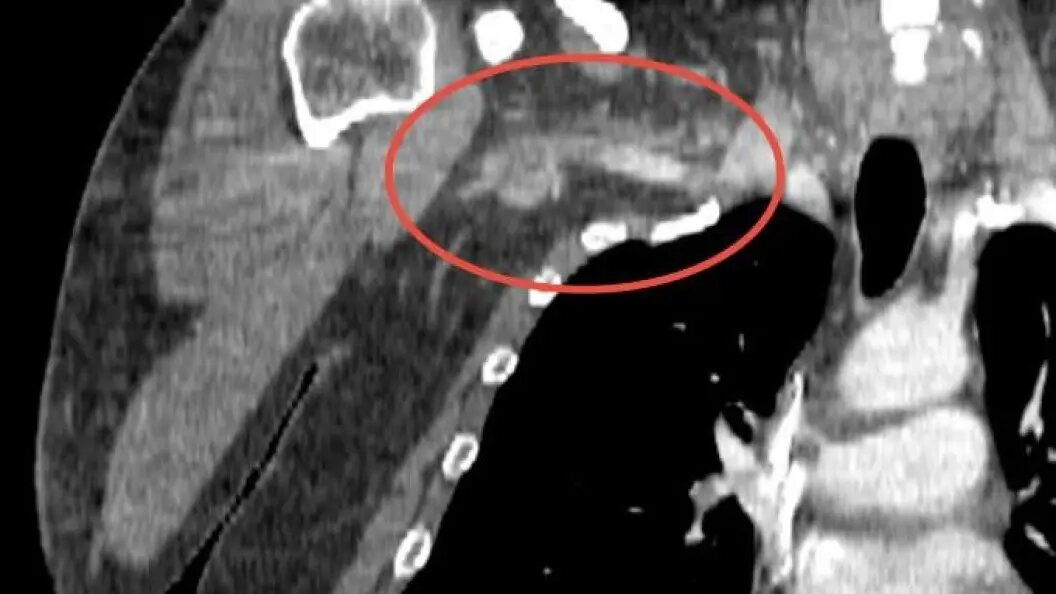

В подмосковном Долгопрудном врачи извлекли из руки пациента тромб длиной 25 сантиметров. Мужчина поступил в больницу с полным онемением правой руки, болями в области плеча и шеи и вспышками в глазах. Как сообщает пресс-служба министерства здравоохранения Московской области, у пациента обнаружили огромный сгусток тромболитической массы, который закупорил сосуды от плеча до шеи. Предположительно тромб образовался из-за нарушения метаболизма, неправильного питания или избыточной массы тела.

Операция по удалению тромба длилась полтора часа. Его извлекли с помощью специального баллона, который продвинул сгусток по сосуду к разрезу в районе локтевого сгиба. Затем врачи зацепили тромб крючком и благополучно вытащили, рассказал сосудистый хирург Михаил Пырля. Сгусток грозил мужчине ампутацией руки, а в случае отрыва части тромба - смертью. После операции функции руки пациента полностью восстановились. Мужчину выписали под амбулаторное лечение.